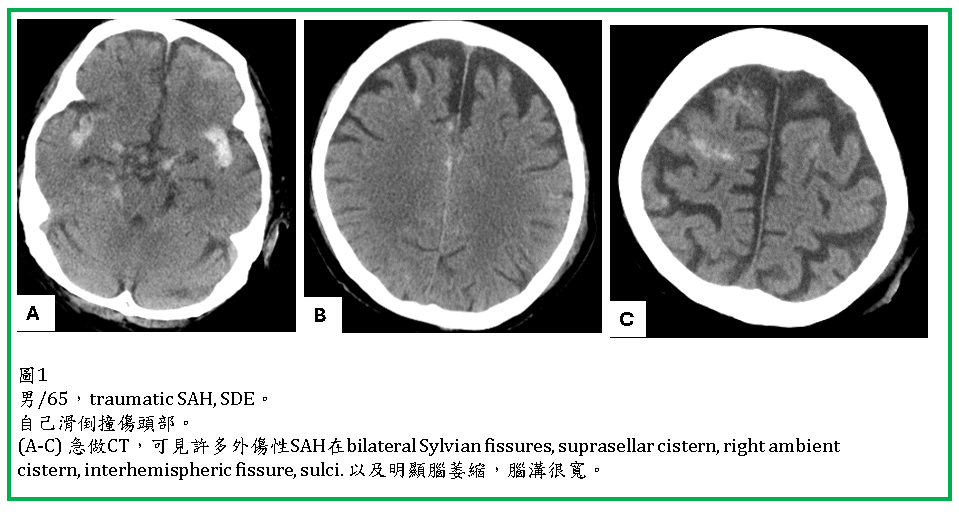

外傷性SAH (Traumatic SAH)

外傷性蜘蛛網膜下腔出血(traumatic subarachnoid hemorrhage, SAH) 很常見,可以單獨發生,但更常合併brain contusion, SDH, EDH。

Traumatic SAH 於CT上常見於大腦腦溝(sulcus),腦裂(Sylvian fissure, interhemispheric fissure),腦池(如suprasellar cistern),以及小腦天幕旁 (tentorial edge)。CT對於SAH及IVH的診斷很敏銳,但在成年人interhemispheric fissures內的falx鈣化與SAH容易混淆。位於tentorium edge 以及interhemispheric fissures內的SAH,與SDH不易區分,coronal reconstruction 有助於鑑別。